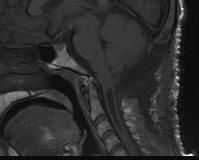

Arnoldi-Chiari Malformation

Congenital abnormality of Cerebellar Tonsils

- herniation of medullary tonsils through foramen magnum into cervical canal

- block CSF flow through foramen Lushka & Malgagne blocked

- often need AV shunt

Type I

- communicating

Type II

- non communicating

- usually larger and associated with spina bifida

2. Hindbrain Herniation / Arnold- Chiari Malformation

- abnormal pressure & circulation of CSF